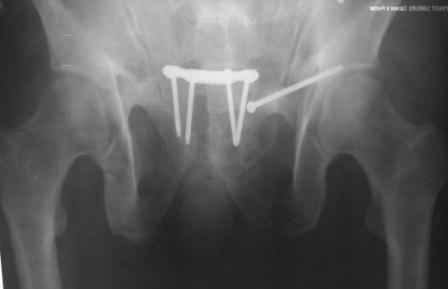

в архиве нашел подобный случай

С Уважением А.Миронов(Новокузнецк)